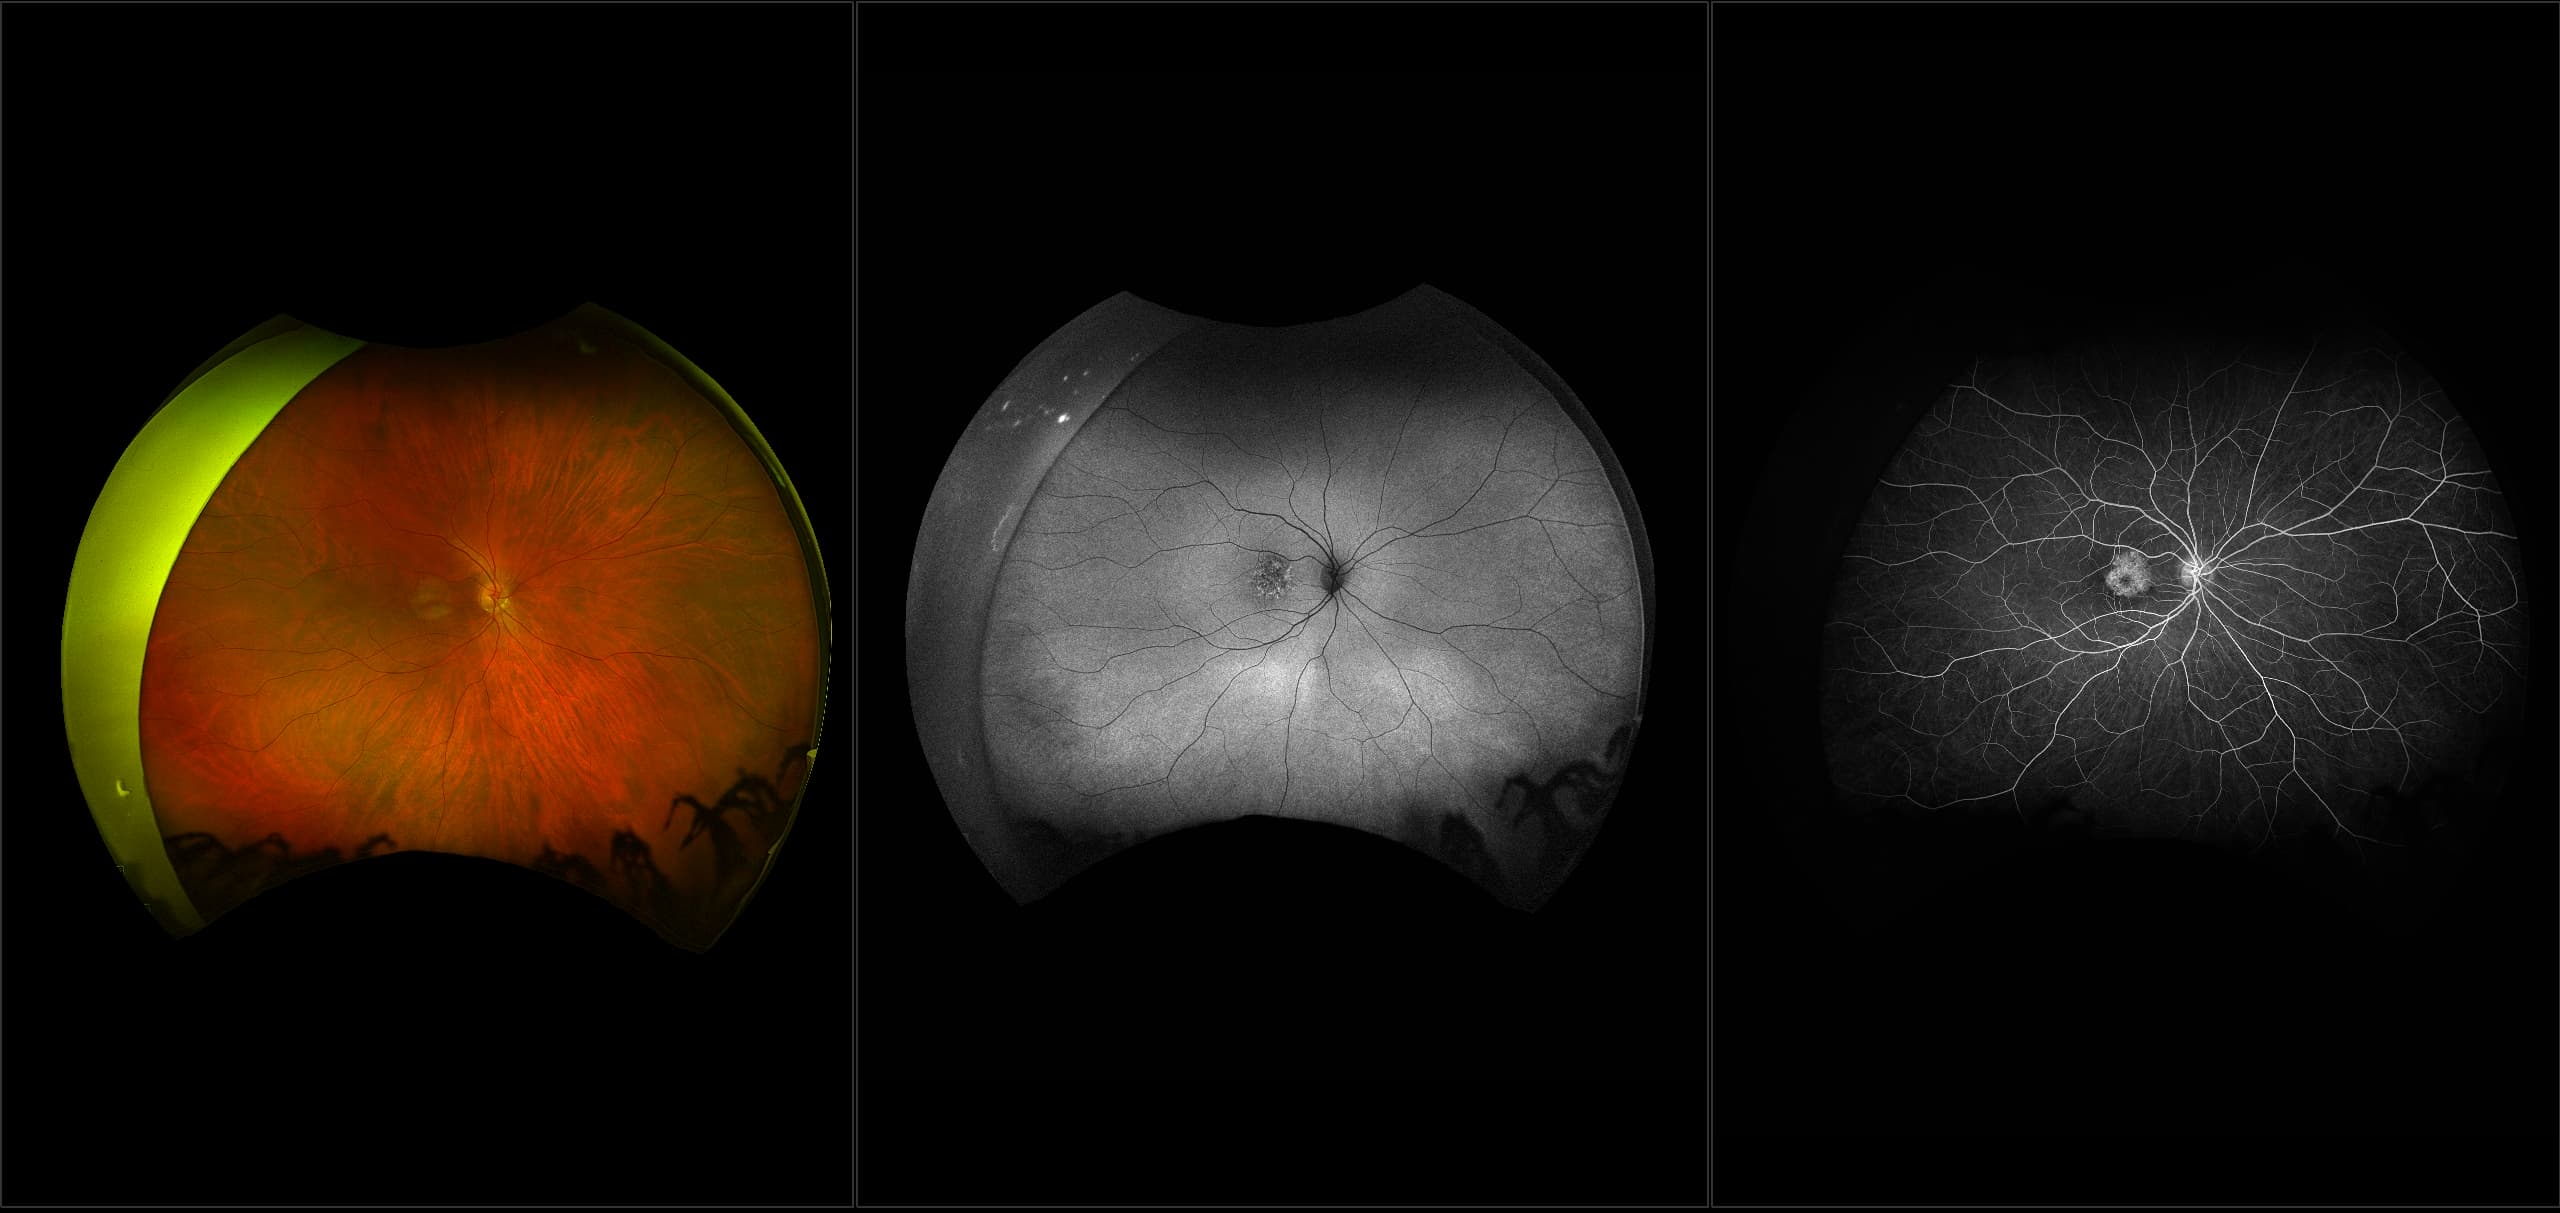

California - Large Pars Plana Cysts - Steered, RG

Pars plana cysts are a common peripheral retinal pathology that do not raise much clinical concern. They do not affect the central vision and observation alone is typically recommended. Pars plana cysts are something to be considered when peripheral retinal elevation is noted on routine exam.